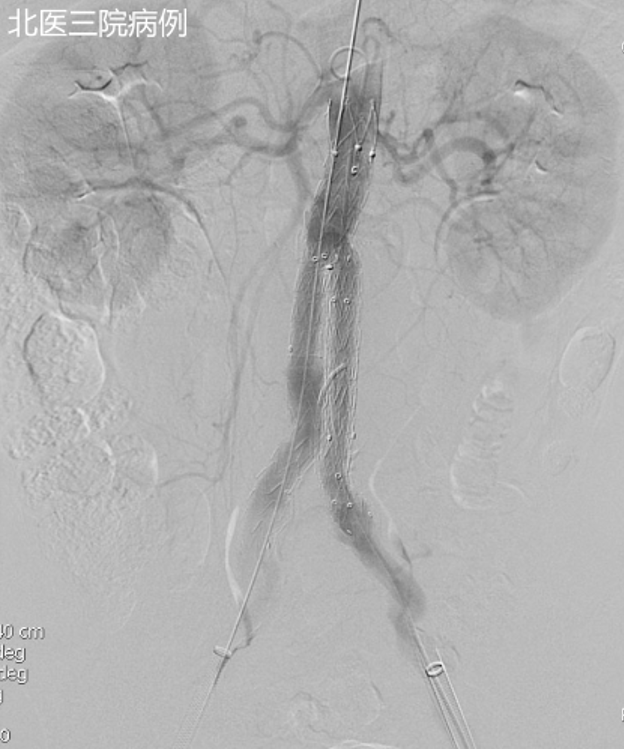

一例术前发现双侧腰动脉,因当时认为“不粗”未处理。术后 CTA 显示 II 型内漏伴瘤体增大。最终经髂内动脉入路,先以弹簧圈构建支架,再注入医用胶封闭瘤囊,成功止漏。

其他补救方法还包括:

经皮直接穿刺瘤囊注射胶;